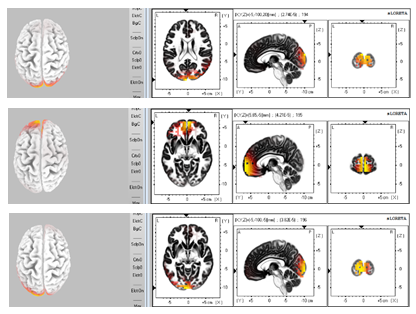

Figure 6:  Delta rhythm activities (From upside to down side, the plots present Delta rhythm activities 240ms, 160ms, 80ms and 0ms before the subject realized the image formation.)

Figure 7:  Performance of Beta rhythm activities (From upside to down side, the plots present Beta rhythm activities 80ms, 70ms, 60ms and 50ms before the subject realized the image formation.)

Figure 8: One cycle of Theta rhythm activity (From upside to down side, the plots present Theta rhythm activities 170ms, 160ms, 150ms, 140ms, 130ms and 120ms before the subject realized the image formation.)

From cortex maps plotted by sLORETA we found that the Delta oscillations are not only the slowest in frequency, but also slowest in the shift or movement of activated regions within the 300ms before subjects realized image formations in their mind. For most of the time in the 300ms, Delta activities tend to arise at either frontal lobe or visual cortex. A sudden shift of activation between these regions would occur for most cases, and a duration of about 150ms to 180ms was observed between two shifts in the analyzed period. A group of plots in Figure 6 presents such Delta wave activities. We also found that the maximum and medium standard deviation of correlation (deduced from sliding window approach as described in the methods section) was highest for the delta wave. This indicates that the brain regions are not consistently correlated and less interactive with each other for the delta wave activity (Figure 5).

Cortex maps plotted by sLORETA also indicate that the Beta oscillation activities show up at frontal and visual cortex as well for most of the sampled time points, but the spatial shifts can be detected every 10ms as shown in Figure 7, which is much faster than that of the Delta oscillation. This is to say for one certain activity map in the 300ms sampled time series, the excited region is different from both 10ms before or after itself for Beta wave. Since the sampling rate of the EEG system is 100Hz, the Beta activity spatial shifts present a frequency of at least 50Hz,

Cortex maps plotted by sLORETA indicate that Theta oscillations do not show a retention at the frontal lobe within the 300ms before the subjects generate images in their mind. However, a detectable annular movement trace can be observed, as displayed in Figure 8, which is transmitting along the edge of the cortex map from its top view. Considering the sampling rate, this trace with Theta wave was continuous during the processing of image formation unlike the sudden shifts of activated regions as seen with the Delta and Beta oscillations. This circulating movement of activated Theta rhythm’s regions would be either clockwise or counter clockwise. The cycle of annular movement varies for different subjects, as well as for different tasks of image formation for the same subject. For most datasets that we recorded from the six subjects, these cycles were between 60ms and 150ms long in duration.